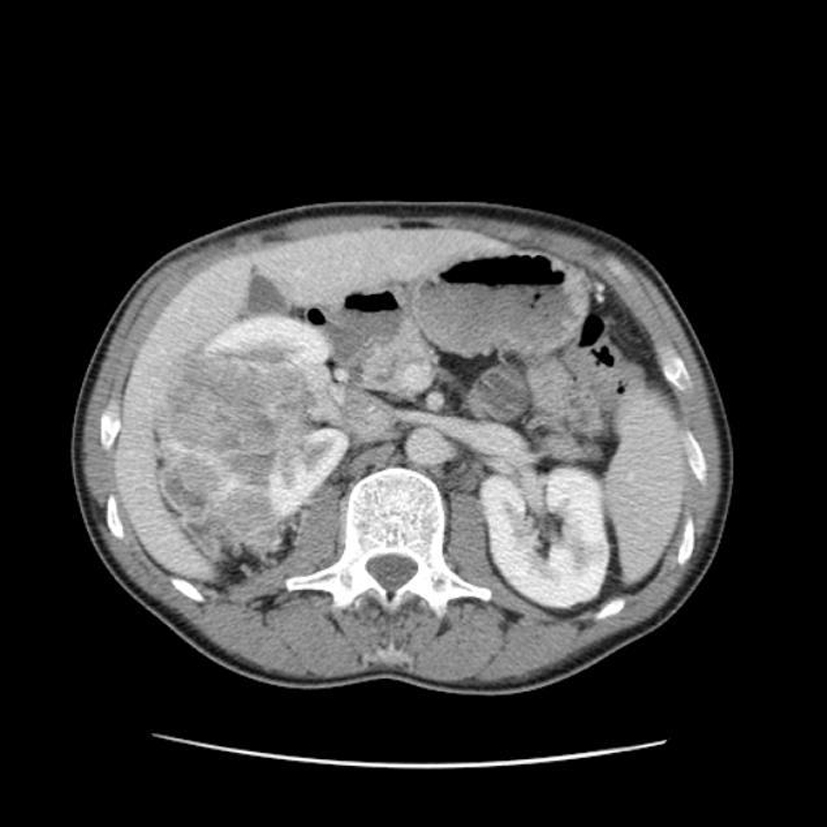

Diagnostic?

volumineuse tumeur rénale droite